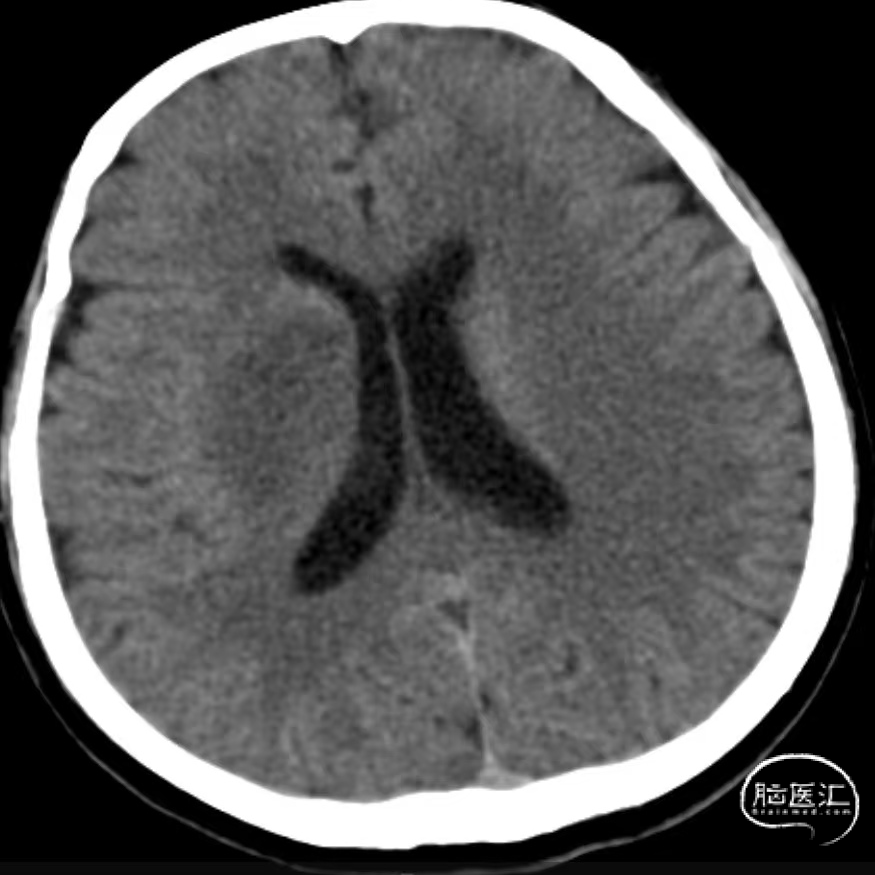

入院时CT:ASPECTS 9分(L1)。